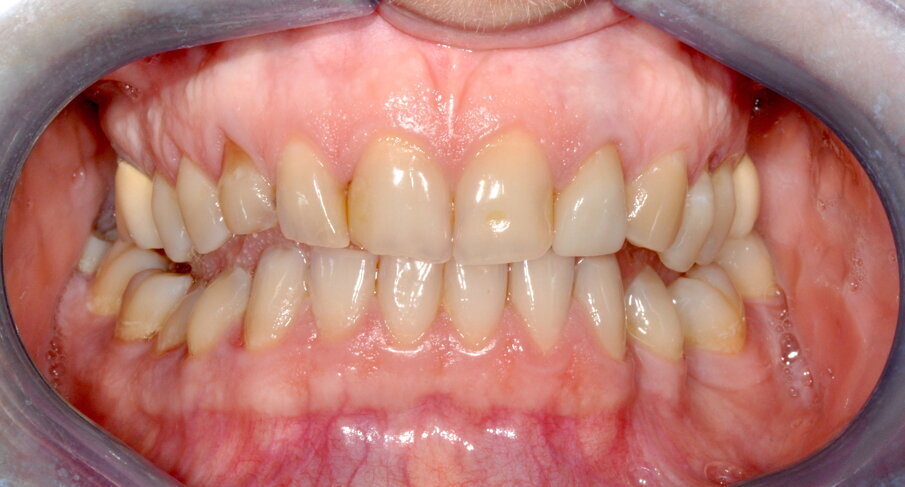

Paziente di sesso femminile, 30 anni, non fumatrice, con anamnesi sistemica silente, assenza di allergie a farmaci e sostanze alimentari, familiarità materna per malattia parodontale.

Si presenta alla nostra attenzione lamentando alitosi, mobilità e ipersensibilità dentale.

Viene perciò effettuata una visita parodontale completa con compilazione della cartella parodontale, set fotografico e raccolta dello status radiografico. Il profilo di rischio parodontale della paziente, stilato in base ai criteri del Periodontal Risk Assessment1 risulta essere di tipo “alto”. Vista la perdita di attacco clinico (CAL) nel sito con maggiore interessamento (≥5 mm), la perdita ossea valutata radiograficamente (RBL), la progressione della malattia (valutata “moderata”), la diagnosi è di Parodontite Generalizzata di Stadio IV e Grado B2. Osservando la cartella parodontale si può notare una maggiore progressione della malattia nei sestanti III, IV e VI con sondaggi superiori ai 6 mm a carico degli elementi 2.4, 3.6, 3.7, 4.4, 4.5, 4.6. e 4.7, BOP (Bleeding on Probing) positivo e SOP (Suppuration on Probing) positivo nei siti 2.4. e 4.6.

Fig. 1 - Fotografia frontale al T0.